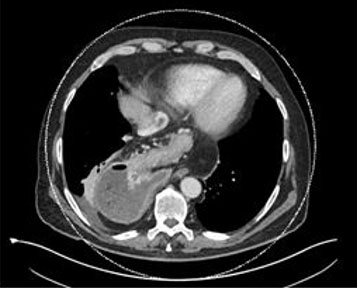

We report the case of a 74-year-old male patient who presented with vomiting, appetite loss, and hematemesis for ten days. A gastroscopy performed two weeks earlier showed grade A esophagitis and a mixed hiatal hernia with sliding and para-esophageal components. We performed another gastroscopy on arrival at the emergency room, which showed grade D esophagitis and a stomach located almost entirely in the thorax. There also was an important alimentary stasis. The CT scan displayed an intra-thoracic stomach positioned on the right side of the chest (Figure 1). From the upper gastrointestinal series, we can clearly see that two-thirds of the stomach are intra-thoracic, with an important dilatation of the esophagus associated (Figure 2). Considering the symptomatology, we decided to perform a laparoscopic hernia repair.

Figure 1: Abdominal CT-scanner showing the intra-thoracic stomach.